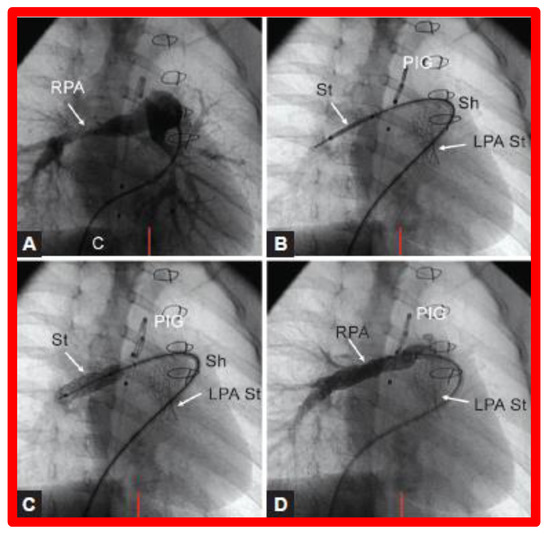

Figure 26.

(A). Cineangiographic frames in a 30° right anterior oblique view illustrating long-segment right pulmonary artery (RPA) stenosis (arrow) before implantation of stent (St). The position of the St prior to (B) and following (C) balloon inflation to implant the St are shown. (D). Angiography following St implantation shows improvement. Note trivial residual narrowing (top arrow) in (D). C, catheter; LPA St, left pulmonary artery stent implanted just prior to RPA stent implantation. Sh, sheath; PIG, pigtail catheter. Reproduced from Reference [98].